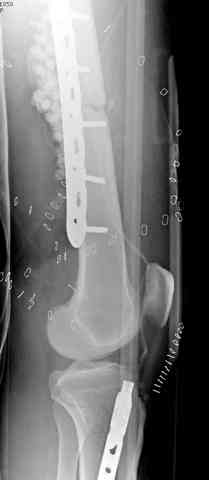

Я бы выполнил более стабильную фиксацию (а у меня есть подозрения в нестабильности отломков - компоновка минимальная, стержни проведены близко друг от друга, имеется выраженное воспаление тканей вокруг раны). Добавил бы стержни в данном аппарате или бы наложил спицестержневой аппарат.

Наверное, оптимальное решение для закрытие раны на данном неудобном уровне - микрохирургическая пересадка мышечного или кожно-мышечного лоскута (рис. 1, 2, 3).